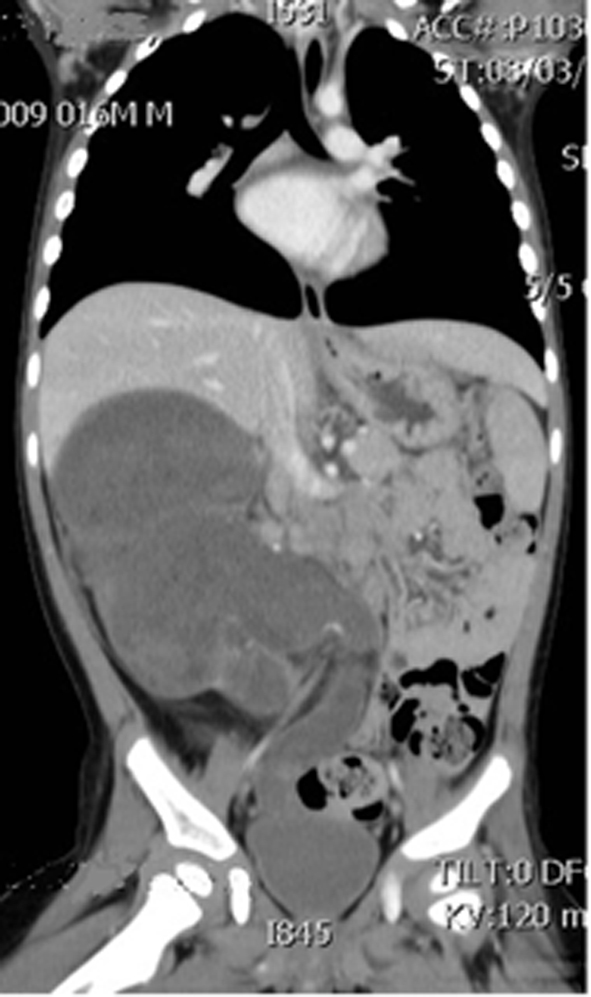

Wilms’ Tumor With Transureteric Extension Into Bladder